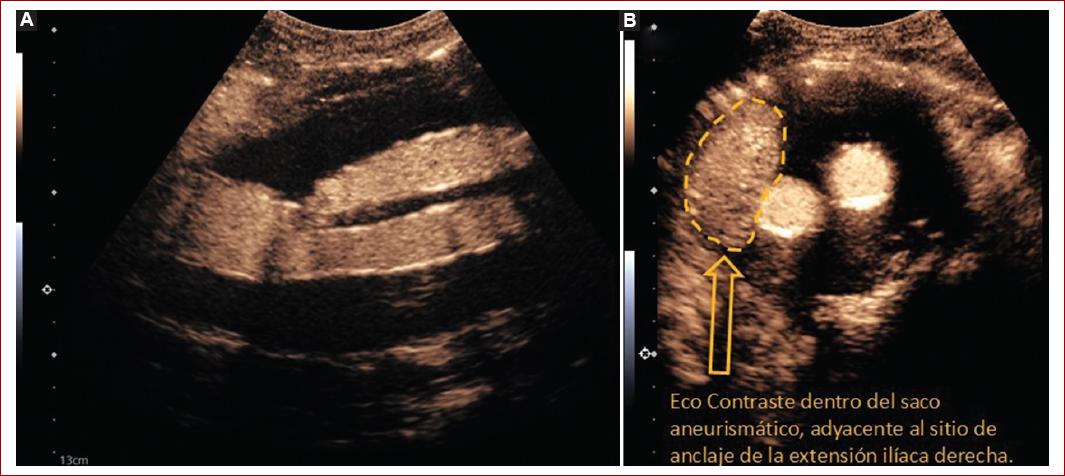

- En una vena periférica (cefálica o mediana), con un catéter 18 G, se inyectan 2.5 ml de contraste (SonoVue 8), seguido de un bolo de 20 cc de solución de salina al 0.09%. Se realiza análisis en tiempo real, cronometrado (Fig. 5).

- Se evalúa sitio de anclaje proximal, así como anclaje distal de las extensiones ilíacas.

- El tiempo de aparición de burbujas de contraste en el saco aneurismático, < 10 s es indicativo de endofuga I o III; en cambio, un tiempo > 15 s es indicativo de endofuga tipo II. Respecto a la dirección del flujo: centrípeto es sugestivo de endofuga tipo II, centrífugo es sugestivo de endofuga tipo I o III (Tabla 3).

Figura 5 Evaluación de ultrasonido contrastado. A: aplicación de microburbujas, como contraste, el sitio de fijación proximal sin datos de endofugas tempranas ni tardías. B: endofuga tipo IB (flecha amarilla), de realce temprano (< 5 s) adyacente a la extensión ilíaca derecha.